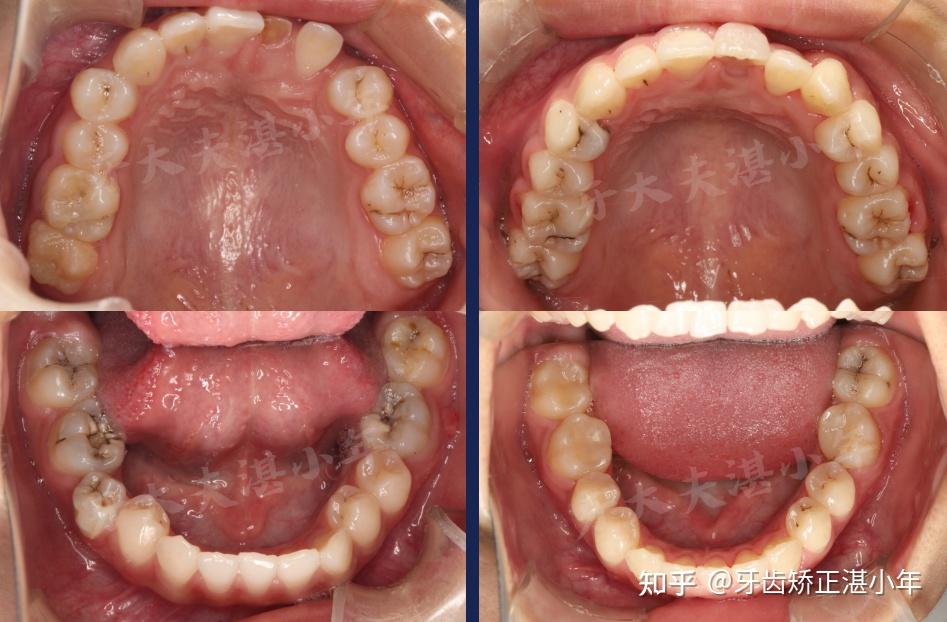

咬合片

【牙科摄影】上颌咬合面的口腔摄影 摄影要点